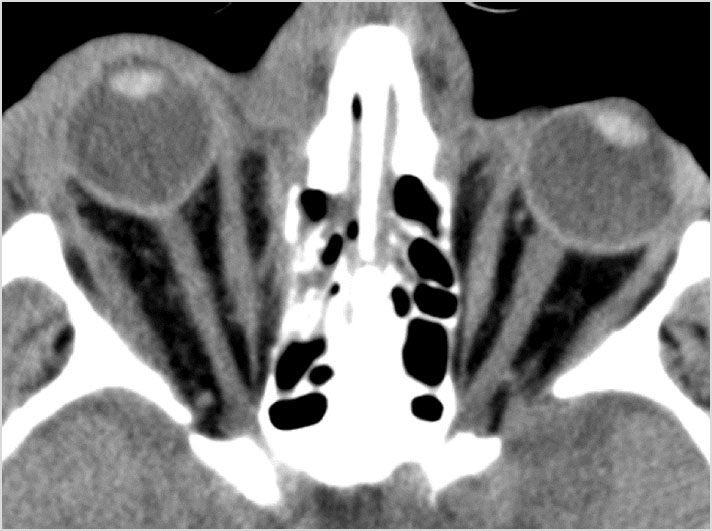

Midface - Maxillary region

There is evidence of a midface injury.

Fronto- naso - ethmoidal complex

There is injury of the fronto-nasal- ethmoid complex. Specifically, the ethmoid roof, olfactory fossa and the cribriform plate are fractured and/or significantly dehiscent.

The frontal bone and frontal sinus inner and outer tables are fractured.